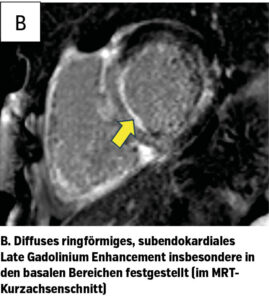

Insbesondere zeigte sich in der MRT das Vollbild einer kardialen Amyloidose (Abb. 1b). Ebenso auffällig war das erhöhte Extrazellulärvolumen, die septale Wanddicke und ein kleiner fokaler Perikarderguss. Diese Befundkonstellation lässt sich durch eine ausgeprägte diastolische Dysfunktion infolge der Amyloidablagerungen erklären – bei einer mäßiggradig eingeschränkten LVEF von 49%.